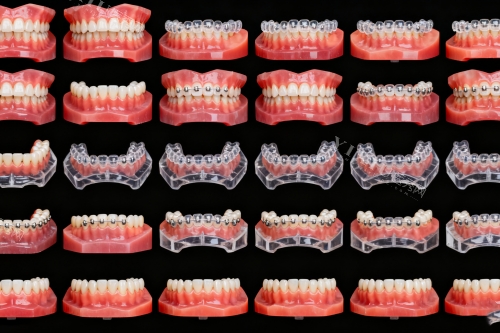

牙齿矫正技术的进步为患者提供了更多选择,隐形牙套和传统金属托槽是目前较主流的两种矫正方式。了解它们的区别有助于根据个人情况做出合适选择。

外观差异较为直观。隐形牙套采用透明高分子材料制成,佩戴后几乎不可见,满足了成年患者对美观的追求。而金属托槽则较为显眼,但现代托槽体积已大大缩小,且有些医院提供陶瓷托槽选项,美观度有所提升。

适合人群方面,隐形牙套特别适合对外观要求高的职场人士和大学生。而青少年患者往往更适合金属托槽,因其能够更好地处理生长发育期的复杂牙齿移动。重的错颌畸形患者也可能需要金属托槽的***矫正力。